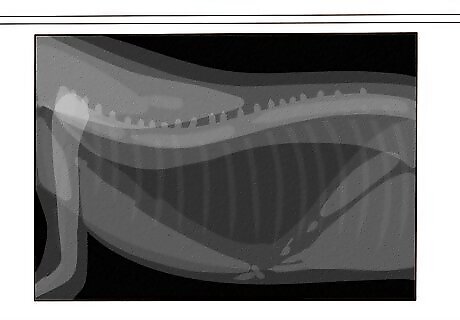

Your vet will order X-rays and CT scans to rule out other causes. Feline asthma is a diagnosis of exclusion, meaning a vet can only determine it is asthma by ruling out the other common causes of respiratory distress in cats. The vet will perform various diagnostic tests, such as chest X-rays and CT scans, to diagnose the asthma. Once your vet has made the diagnosis, they will discuss the various treatment options with you. Other potential diagnoses include bronchitis, cancer, and allergies. Unless your cat has an asthma attack in front of your vet, it may be difficult for your vet to diagnosis asthma in cats. This is where having a video of your cat in the middle of an asthma attack really helps! While feline asthma is incurable, it is far from a death sentence. Don’t worry—things will be okay so long as you get treatment.